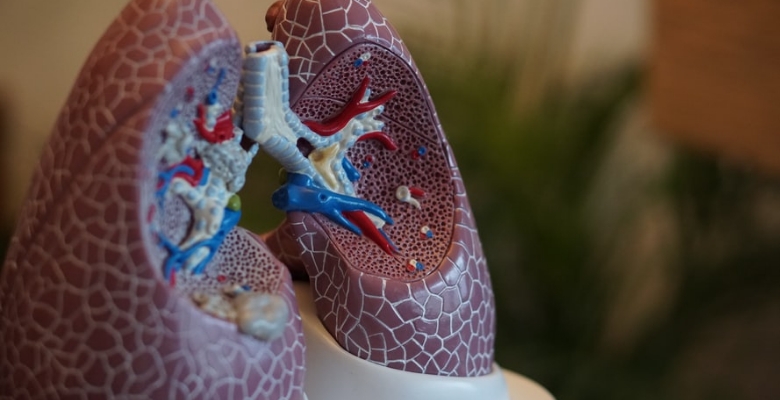

No âmbito do “COVID-19 EGFR Support Program”, a AstraZeneca Portugal, a Biocartis e a Sociedade Portuguesa de Anatomia Patológica estabeleceram um acordo para a disponibilização gratuita de 204 testes que permitem saber, em apenas duas horas, se o doente com cancro do pulmão é positivo para a mutação EGFR, um fator determinante para a decisão terapêutica.